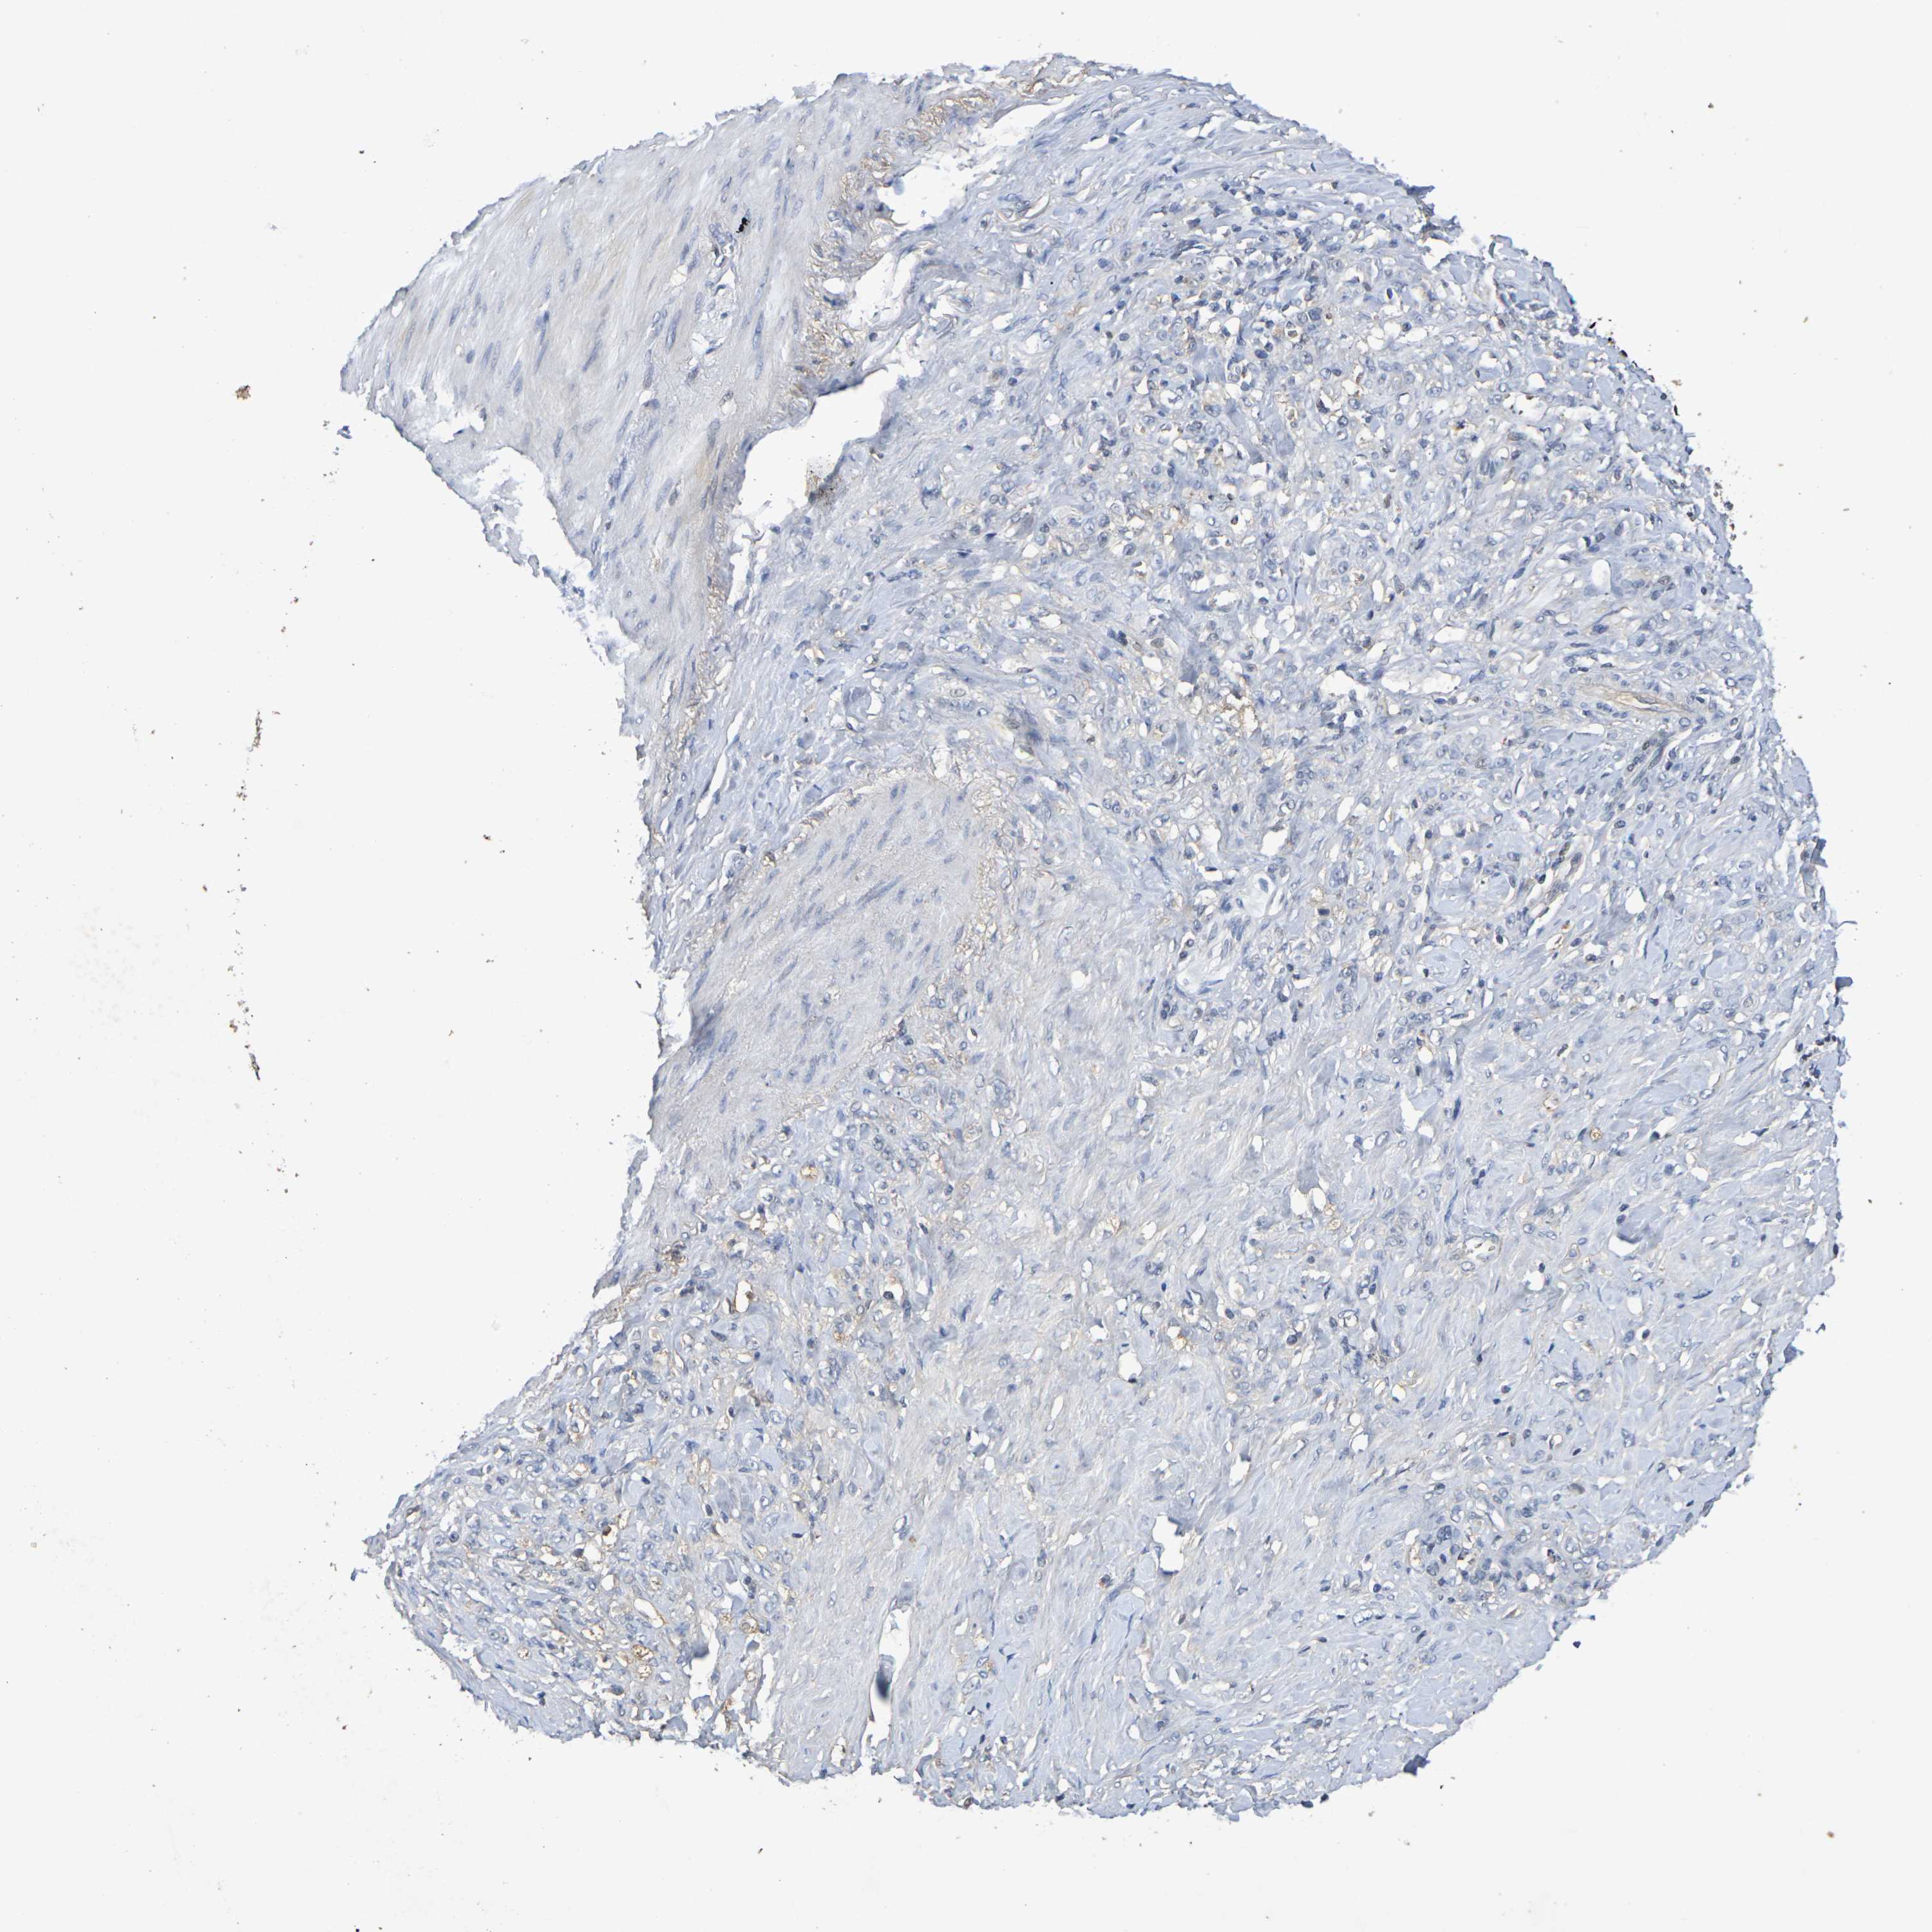

STOMACH CANCER - Protein expressioni

A mouse-over function shows sample information and annotation data. Click on an image to view it in a full screen mode. Samples can be filtered based on level of antibody staining by selecting one or several of the following categories: high, medium, low and not detected. The assay and annotation is described here.

Note that samples used for immunohistochemistry by the Human Protein Atlas do not correspond to samples in the TCGA dataset.

Antibody stainingi

Antibody staining in the annotated cell types in the current human tissue is reported as not detected, low, medium, or high, based on conventional immunohistochemistry profiling in selected tissues. This score is based on the combination of the staining intensity and fraction of stained cells.

Each image is clickable and will lead to virtual microscopy that enables deeper exploration of all samples and also displays staining intensity scores, fraction scores and subcellular localization as well as patient and tissue information for each sample.

Antibody HPA001907

Antibody HPA002735

Antibody CAB010451

Antibody CAB080271

Staining

High

Medium

Low

Not detected

Intensity

Strong

Moderate

Weak

Negative

Quantity

>75%

75%-25%

<25%

None

Location

Nuclear

Cytoplasmic/membranous

Cytoplasmic/membranous,nuclear

Adenocarcinoma, NOS

Adenocarcinoma, High grade